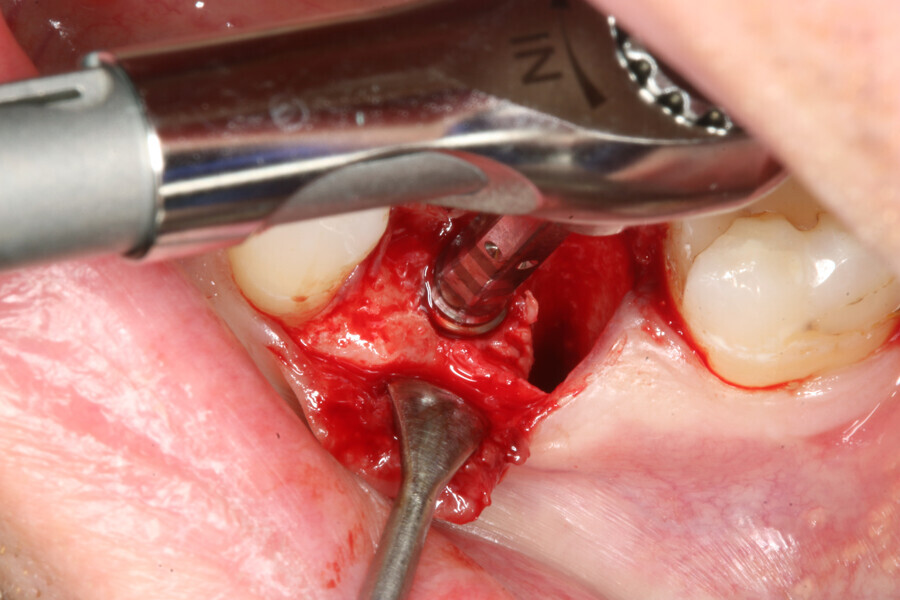

The implant site was prepared following the recommended drilling protocol for the planned PrimeTaper EV 4.2 mm diameter implant (drills #1, 3 and 4; Fig. 2). After cortical preparation with drill #5, the implant was placed. The preparation was finalised with a tap, owing to dense trabecular bone (Fig. 3). The implant was inserted to a torque of 42 Ncm (Fig. 4).